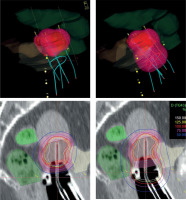

Fig. 1

Isodose surface (light red) of the prescribed dose (top) and dose distribution (bottom) without (left) and with using active dwells in the ring/ovoid of the applicator (right). Pink – IR-CTV; Red – HR-CTV; Grey – GTV; Yellow – bladder; Dark green – rectum; Light green – sigmoid

In the era of advanced imaging modalities, special IS-IC applicators with the opportunity of oblique needles and inverse dose optimization methods, there is no strong evidence available for implementing one approach over another. Tanderup et al. recommended dose planning aims and dose prescription in image-guided cervical BT [45]. However, these conclusions were based on the clinical evidence of treatment plans using the traditional pear-shape spatial dose only. Earlier, the same team tried to de-escalate the vaginal dose by decreasing dwell times in R/O and increasing it in tandem/needles [27]. The aim was to maintain the target dose while reducing the dose to the surface of the vagina to be < 140% of the physical fractional BT dose corresponding to a total EQD2 of 85 Gy. The R/O loading was reduced from 51% to 33% of total loading, which resulted in a reduced dose to ICRU recto-vaginal point by a mean of 4 ±4 Gy EQD2, and D2 doses to the bladder and rectum were reduced by 2 ±2 Gy and 3 ±2 Gy, respectively. In the current study, we achieved the total dose de-escalation of the critical tissues, as source loading in the R/O channel of the applicators was reduced to zero in cases where residual tumors did not involve the vagina. This approach simply follows the basic rule of BT that active dwell positions have to be inside or on the surface of the target volume. This technique results in a highly conformal tumor-shape dose distribution around the target volumes, breaking the rules of the conventional pear-shape dose (Figure 1).

Basically, the distance of the R/O source path from HR-CTV and from OARs is a good starting point to decide the activation of R/O. If the surface of the R/O part of the applicator touches the inferior border of HR-CTV, the former distance is 5-10 mm, depending on the applicator used. Especially in the case of a narrow vagina, an air gap can exist between R/O and the surface of HR-CTV (Figure 1), which may affect the use of vaginal component. It strongly influences dosimetric parameters, mainly dose conformality of the plans. If after dose optimization the dose exposition is higher to an OAR than to HR-CTV, an alternative dose plan is recommended without activation of R/O as well as evaluation of the fulfilment of dose recommendations in both the plans. The necessity of loading R/O strongly depends on an individual anatomy of a patient. Of note, in case of tumors with vaginal involvement, when HR-CTV includes a portion of the vagina, source dwell positions in R/O (in HR-CTV) has to be activated accordingly the basic rules of BT. However, majority of residual tumors of the cervix does not involve the vagina. In this case, the R/O part of the applicator can be only a template for IS needles, or a fixation tool for the intra-uterine tandem.